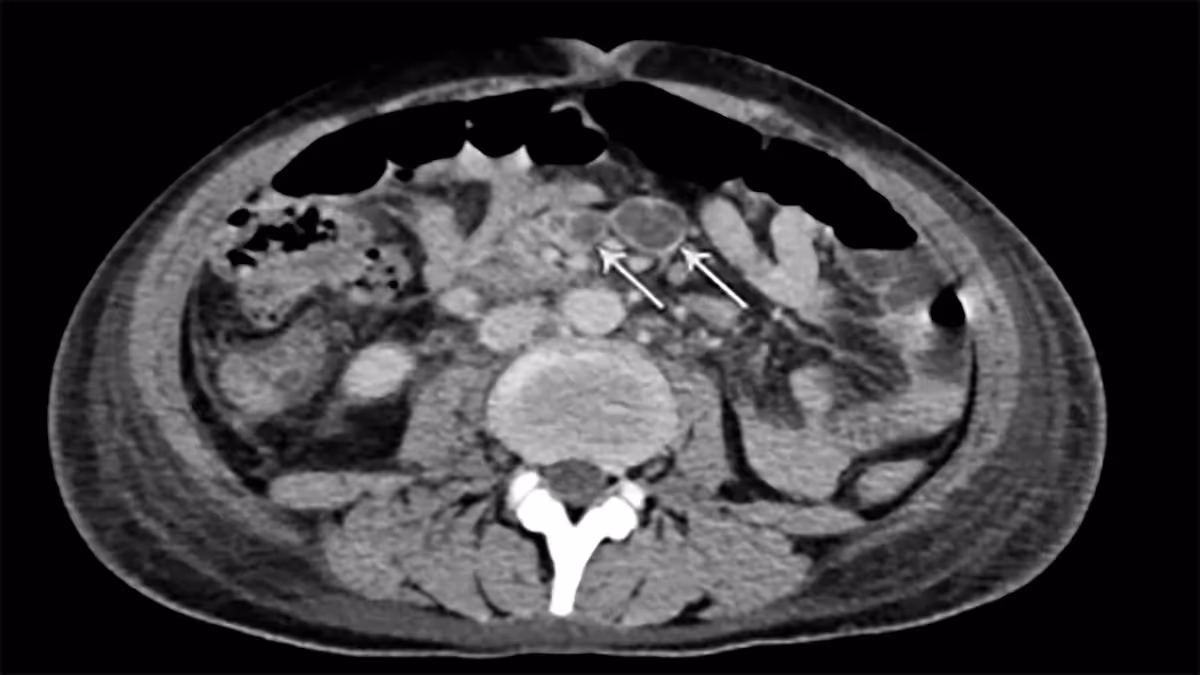

Em casos de suspeita clínica, o exame de imagem de escolha é a tomografia computadorizada de abdome. Os principais achados são: espessamento circunferencial e assimétrico de segmentos intestinais (podendo ter áreas de estenose – Sinal de Stierlin), linfonodomegalia abundante com centro liquefeito ou necrótico (necrose caseosa), sinais inflamatórios em planos gordurosos adjacentes.

Pode ter, ainda, outros acometimentos de TB abdominal ou sinais de TB pulmonar. O envolvimento de órgãos sólidos se manifesta como múltiplos pequenos nódulos hipoatenuantes vistos na superfície e em todo o parênquima.